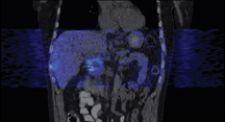

“We’ve taken it one step further with 4-D PET and now have the PET image overlaid with 4-D data to see both anatomy and function,” Dr. Heron explained. “This provides a wealth of data that is absolutely amazing.”

Dr. Heron cites a specific clinical example of 4-D CT/4-D PET imaging’s impact on patient treatment planning. In a patient with an upper abdominal mass, Dr. Heron could not conclusively tell exactly where the tumor was on a typical helical CT scan. He could see the tumor with PET. However, once he fused the images and created a 4-D PET/CT data set, Dr. Heron could identify nearby lymph nodes that weren’t obvious on the helical CT, 4-D CT or PET scans.

“This information dramatically changed our treatment plan for the patient. With the 4-D data, we learned the center of the tumor was hypoxic, and, therefore, we could use that knowledge to deliver more radiation to the center of the tumor,” indicated Dr. Heron.